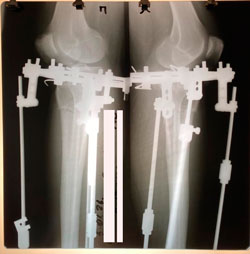

на фиксации

Вложения

image-26-12-20-12-00-5.jpg

image-26-12-20-12-00.jpg

рентген перед фиксацией

image-05-01-21-06-30-4.jpg

image-05-01-21-06-30-5.jpg